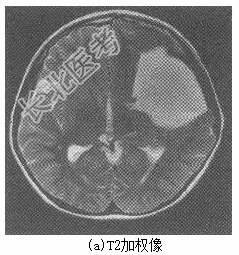

患儿男性,9岁。因“反复头痛半年,加重1天”入院。缘于入院前半年无明显诱因出现阵发性头痛,以左侧颞部明显,呈闷痛样性质,未向他处放射,每次持续约数分钟至半小时不等,尚可忍受,休息后可缓解,无发热、呕吐、四肢抽搐,无偏瘫、失语、智力异常等,未重视未诊治。1天前上述症状加重,部位及性质同前,发作更为频繁,无法正常学习、生活。病程中,食欲尚可,二便正常。体格检查T36.7℃,P98次/min,R20次/min,BP96/58mmHg。神志清楚,言语清晰,对答可,记忆力、定向力、反应力正常。头围54cm,头颅外观无畸形。双侧瞳孔等大等圆,直径约3.0mm,对光反应灵敏,双眼各向活动正常。双侧额纹对称,口角无歪斜,伸舌居中。颈软,心肺腹部查体无明显异常,四肢肌力及肌张力正常,双侧病理征阴性,脑膜刺激征阴性,小脑征阴性。辅助检查头颅CT平扫(图6-38)提示左侧颅中窝蛛网膜囊肿。头颅MRI平扫(图6-39)提示左侧颅中窝占位性病变,大小为8.0cm×6.5cm×6.4cm,考虑蛛网膜囊肿。

图6-38头颅CT诊断左侧颅中窝蛛网膜囊肿。